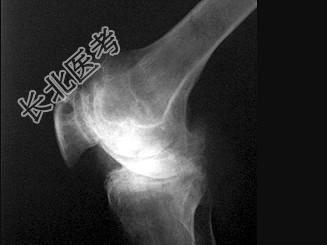

- 单项选择题男,21岁, 慢性膝关节疼痛,活动受限, 皮肤多处青紫,结合图像, 最可能的诊断是 ( )

A、痛风

B、类风湿关节炎

C、退行性骨关节病

D、白血病

E、血友病性关节炎